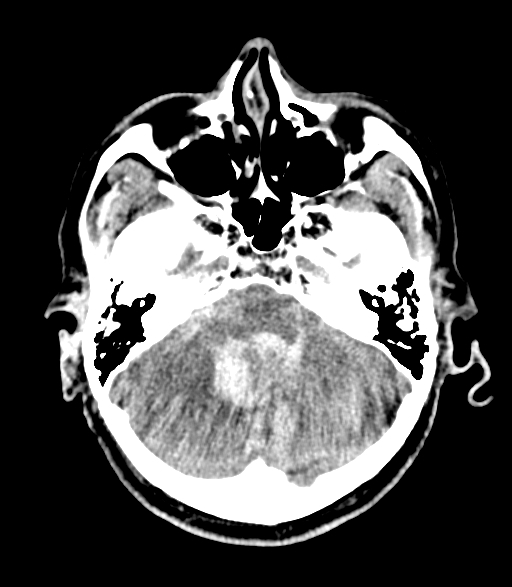

致密颅底导致的射束硬化伪影致密颅底导致的射束硬化伪影

脑部扫描的环形伪影脑部扫描的环形伪影